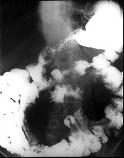

问题 女,28岁,腹痛,恶心呕吐,大便潜血阳性,轻度腹胀,中腹部可扪及一不规则肿块,影像表现如图,最可能的诊断是()

选项 A.小肠腺癌 B.小肠非霍奇金淋巴瘤 C.小肠Crohn病 D.小肠结核 E.腹膜后淋巴结结核

答案 B